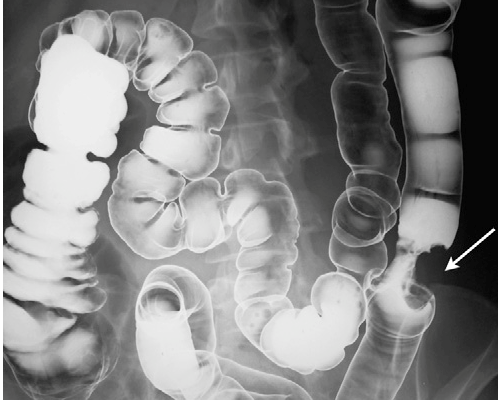

Colonoscopia este investigaţia de primă intenţie, deoarece permite atât localizarea leziunii/leziunilor, prelevarea de biopsii pentru diagnostic histopatologic, cât și un eventual abord terapeutic al leziunilor rezecabile endoscopic. Nu trebuie omis faptul că un procent de 2-6% din tumori pot scăpa...

Cancerele colonului stâng evoluează predominant circumferențial, producând îngustarea intestinului, ceea ce determina modificări ale tranzitului și adesea rectoragii. Tumorile care apar în această zonă tind să împiedice pasajul normal al scaunului, ducând la apariția durerilor abdominale, constipație care poate alterna...